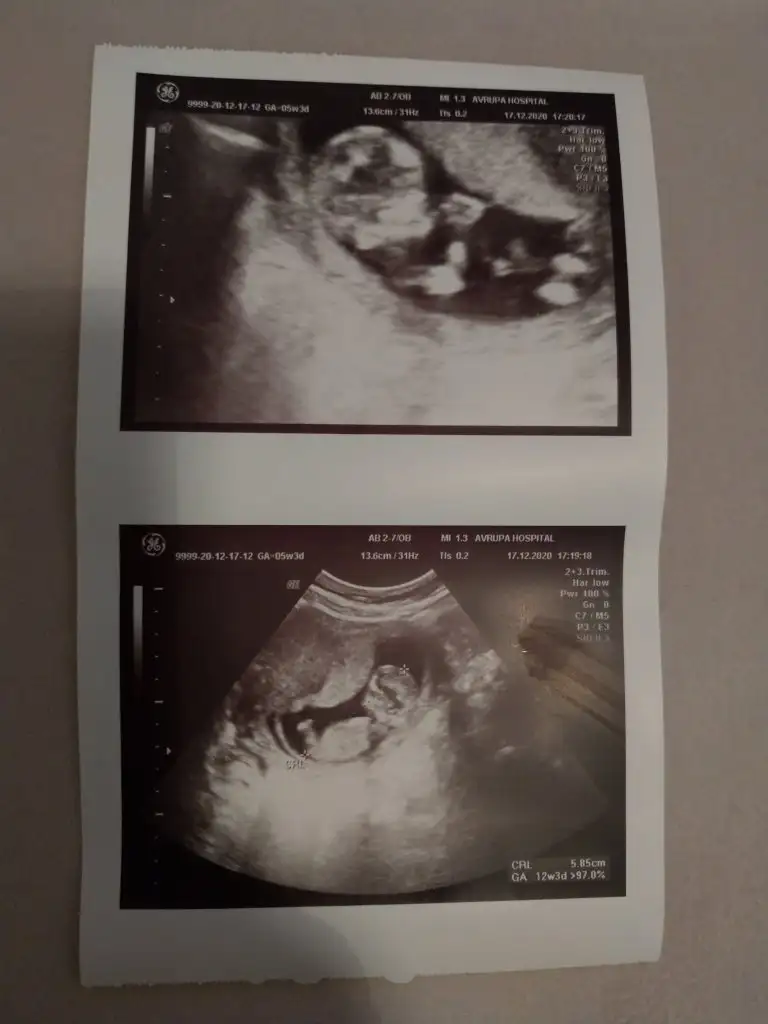

İkinci bebeğime hamileyim birinci ultrason fotosu ilk bebeğim ikinci ultrason şuanki ikinci yavrumun ikiside 5 haftalık görüntü ilk bebeğim erkek kese yuvarlak ikinci bebeğim daha henüz belli değil 5 haftalık 😌 merak ettim baktım ama maalesef bende tutmadı yuvarlak uzun teorisi 😀

Ya 12.haftada kız gibi dedi ama bacağıyla kapattı. Yani kesin bir şey söylemedi ve bence de o haftalarda çok erken. Yanılmalar çok oluyo. Bir ay sonraya randevu verdi cinsiyeti için. Suan yani hala net değil 😶

Öyle canim tabi banada 16 haftada gel dedi. Oğlumdada ozaman net öğrenmiştik. Hayırlısı bakalım☺️